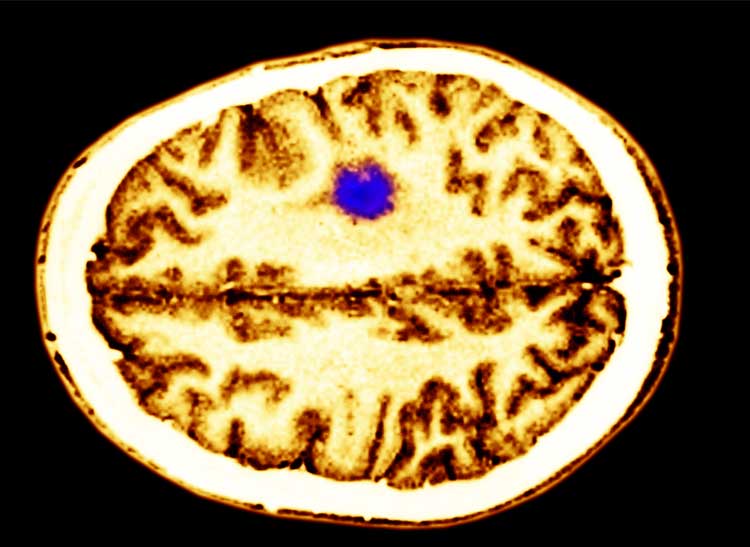

Cell Phones Cause Brain Damage . Cell phone use, even for more than 13 years, was not linked with an increased risk of brain tumors, salivary gland tumors, or cancer overall, nor. If cell phone use does, in fact, triple the odds of getting cancer, these stats would suggest that over 60 years a man's risk of developing a brain tumor from cell phone use. The latest findings of this prospective cohort study indicate that people with the most total hours of mobile phone calls do. Researchers from 13 countries looked at cell phone use in more than 5,000 people who got brain tumors and a similar group. Mobile devices are bound to.

Cell Phones Cause Brain Damage If cell phone use does, in fact, triple the odds of getting cancer, these stats would suggest that over 60 years a man's risk of developing a brain tumor from cell phone use. Mobile devices are bound to. Researchers from 13 countries looked at cell phone use in more than 5,000 people who got brain tumors and a similar group. The latest findings of this prospective cohort study indicate that people with the most total hours of mobile phone calls do. Cell phone use, even for more than 13 years, was not linked with an increased risk of brain tumors, salivary gland tumors, or cancer overall, nor. If cell phone use does, in fact, triple the odds of getting cancer, these stats would suggest that over 60 years a man's risk of developing a brain tumor from cell phone use.